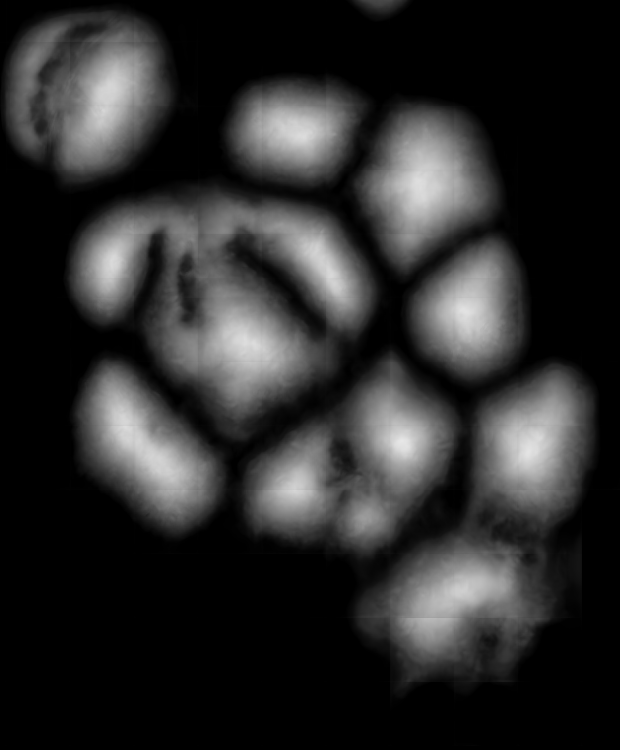

![]() |

| (a) | (b) | (c) | (d) |

Likewise, Fig. 7a shows the maps of calculated outer distances when the ground truths are given. Figs. 7b, 7c, and 7d show the outer distance maps estimated by SingleOuter, DeepDistance, and its extended version, respectively. It is observed that a single-task SingleOuter method is less accurate in estimating outer distances especially for pixels close to cell boundaries. Due to this incorrect estimation, it locates only a single cell for each of the cell pairs shown inside green ellipses, resulting in under-segmentations for these cell pairs. Our multi-task DeepDistance models yield better estimations for these boundary pixels. However, it is important to note that our models do not use the estimated outer distances in a detection algorithm but define this estimation as an auxiliary task. Particularly, this distance is defined to represent a different aspect of the problem and its estimation is considered as complementary to the main task. Concurrent learning of two related tasks with a multi-task model, which uses shared feature representations, better helps avoid local optima. In other words, when two related tasks share the same representations (with a shared encoder path), it is more difficult to finetune these representations for only one of these tasks. This is effective to obtain better learning performances for individual tasks, as also shown in Figs. 6 and 7.